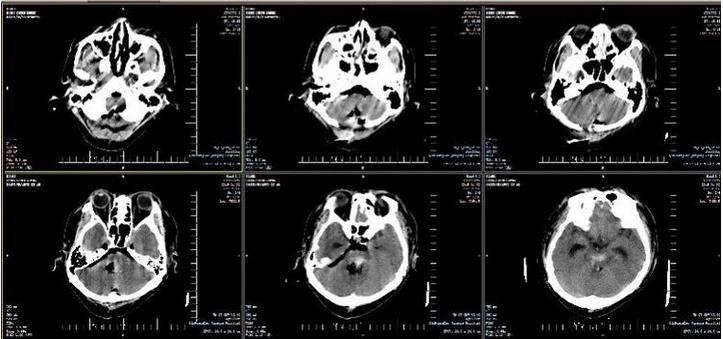

2019年1月2日,军工医院副院长于笑鹏协调急诊科、重症医学科、神经外科、手术室麻醉科做好转接手术患者相关准备工作,紧急召集120急救人员与该医院沟通,将患者接到重症医学科进行术前准备。患者来院后复查头CT显示:脑干内血肿量较前明显增多,出现梗阻性脑积水征象。在院领导的关注下,神经外科医生团队经过两个多小时的精湛手术,患者生命体征平稳。复查头CT显示:脑干内血肿清除彻底,脑积水解除,转回军工医院重症医学科继续治疗。术后6小时,患者自主呼吸恢复,有吞咽动作,格拉斯评分由入院前3分转为5分,各种刺激检测均有反应。

术后头CT片